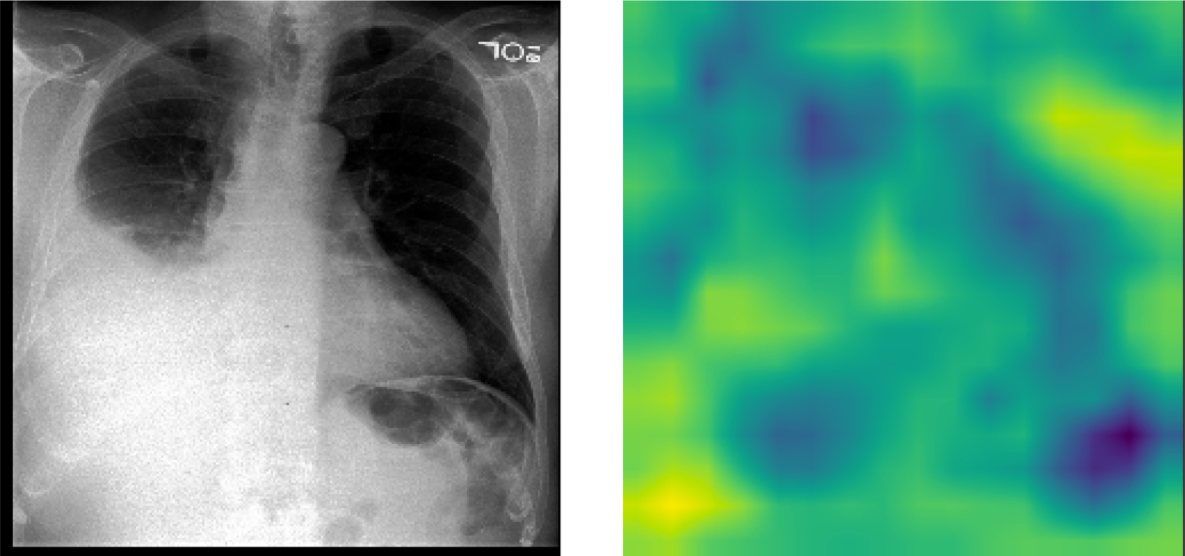

The pre-trained TIMNet used in this study has a text-image matching performance of 74% accuracy and 0.83 auROC. Table I shows the relevant results of the evaluation. Figure 7 shows CAM visualizations of TIMNet on the text-image matching task. The findings of the radiology reports are displayed below the images. The CAMs suggest that the decisions made by TIMNet are reasonable. For instance, in Figure 7(a), the radiology report mentions radiopaque densities in the mid to distal esophagus, and the CAM appears to show that in the middle part of the image. For Figure 7(b), the radiology report indicates increased right-sided pleural effusion, and CAM shows more significant contributions near the effusion areas on the right-hand side of the figure. Figure 7(c) shows a similar correspondence between the CAM-based image segment contributions to the model decision and the textual report.

Refer to caption

(a) FINDINGS: The lungs are clear. There is no pneumothorax nor effusion. Cardiomediastinal silhouette is within normal limits. Radiopaque densities seen in the mid to distal esophagus with additional focus just past the GE junction. This may represent patient’s esophageal pH probe.

(b) FINDINGS: The cardiac, mediastinal and hilar contours appear unchanged. There is no shift of mediastinal structures. There is a large right-sided pleural effusion, which has increased since the earlier radiographs and perhaps slightly since the more recent CT. There is no pneumothorax. The left lung remains clear.

(c) FINDINGS: ET tube is seen with tip approximately 1.8 cm from the carina. Enteric tube seen passing below the inferior field of view. Lower lung volumes are noted on the current exam with bilateral parenchymal opacities which could be due to edema or infection. Prominence of the right hilum is again noted. Moderate cardiomegaly and appears to have progressed since prior could potentially being part due to changes in positioning. No acute osseous abnormalities. Surgical clips project over the left chest wall/axilla.

Figure 7: CAM visualizations of text and image matching on MIMIC-CXR with chest X-ray on the left and CAM on the right. The CAMs reveal that the model focuses on the corresponding areas that show some concerns in the textual findings.